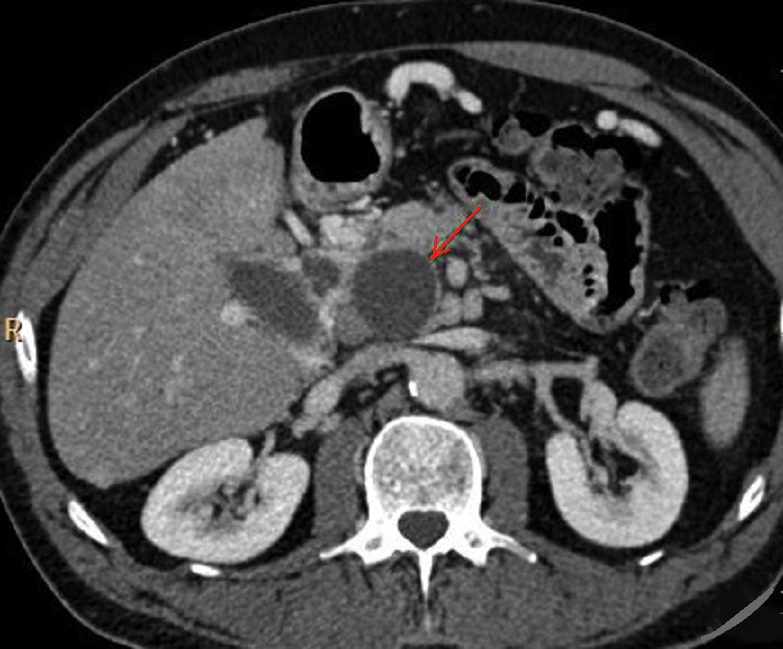

Image radiologique TDM d'une pseudo kyste du

pancreas a aspect lesionaire est un kyste arrondie

volumineuse a hypodense , a bord regulier , lisse ,

fine situe a la tete du pancreas ( fleche rouge ) .

Coupe TDM axiale |